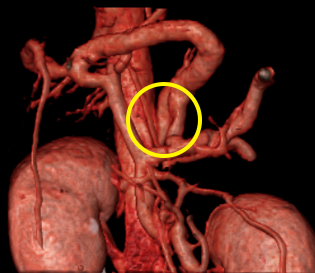

CT촬영을 통한 PSS 질환 진단